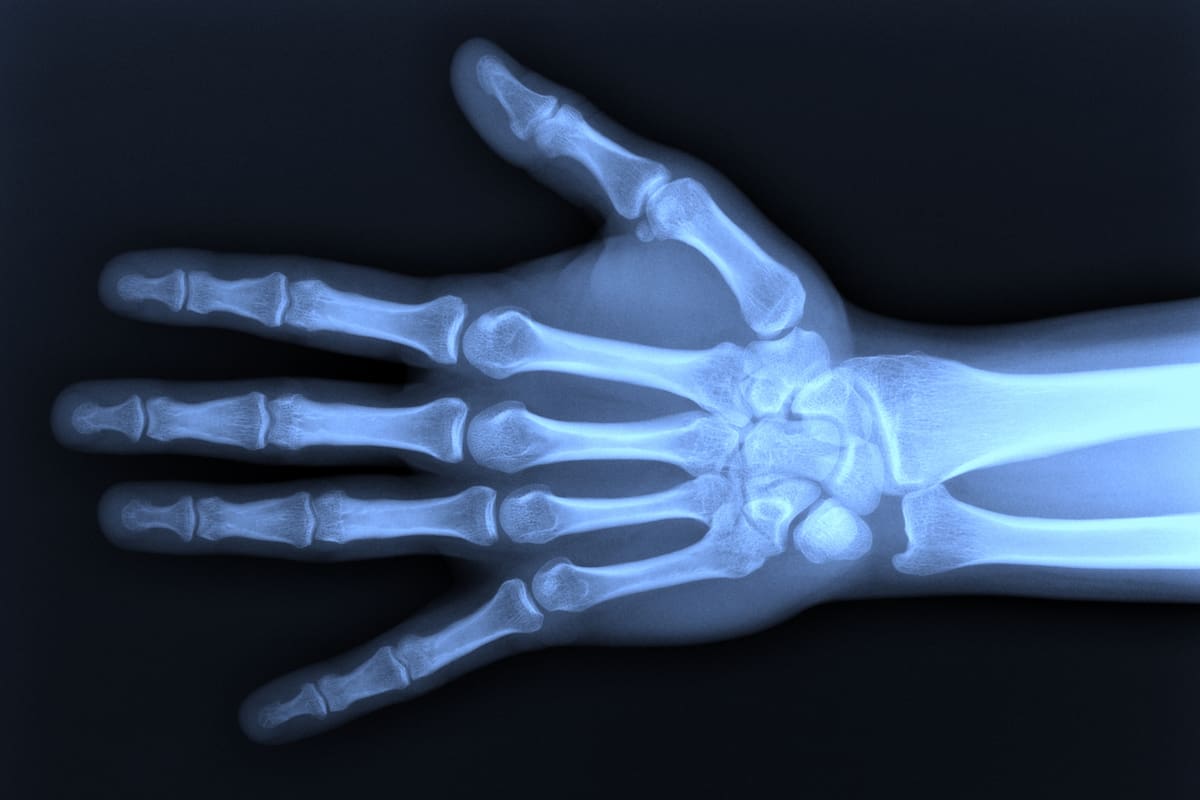

La técnica de bioimpedancia se basa en aplicar una corriente eléctrica a través de la parte del cuerpo a estudiar. Esta corriente es inocua e imperceptible, es utilizado para medir el índice de masa corporal y en este caso se emplea para detectar variaciones en las estructuras de los huesos, para saber así si se está ante una fractura.

El prototipo tiene el tamaño aproximado de un celular, con cables que terminan en electrodos adhesivos que se adhieren a las piernas o a los brazos. Pero todavía no es absolutamente portátil: hay que enchufarlo a una PC, y aún no tiene desarrollada una interfaz. Cuando esté terminado, “tendrá el tamaño de una Playstation portátil y podrá mostrar los resultados en el momento, descartando falsos positivos y permitiendo actuar a los rescatistas o a las ambulancias de otra manera”, sostiene Dell’Osa.